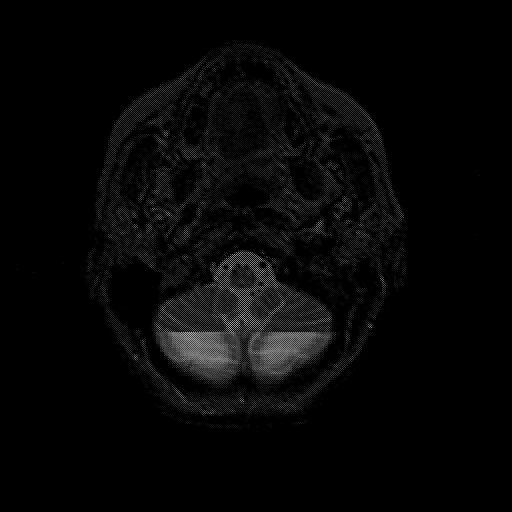

overlay : Slice 6

Slice 6

MRCBFCBF with

T1PDT2T1PDT2